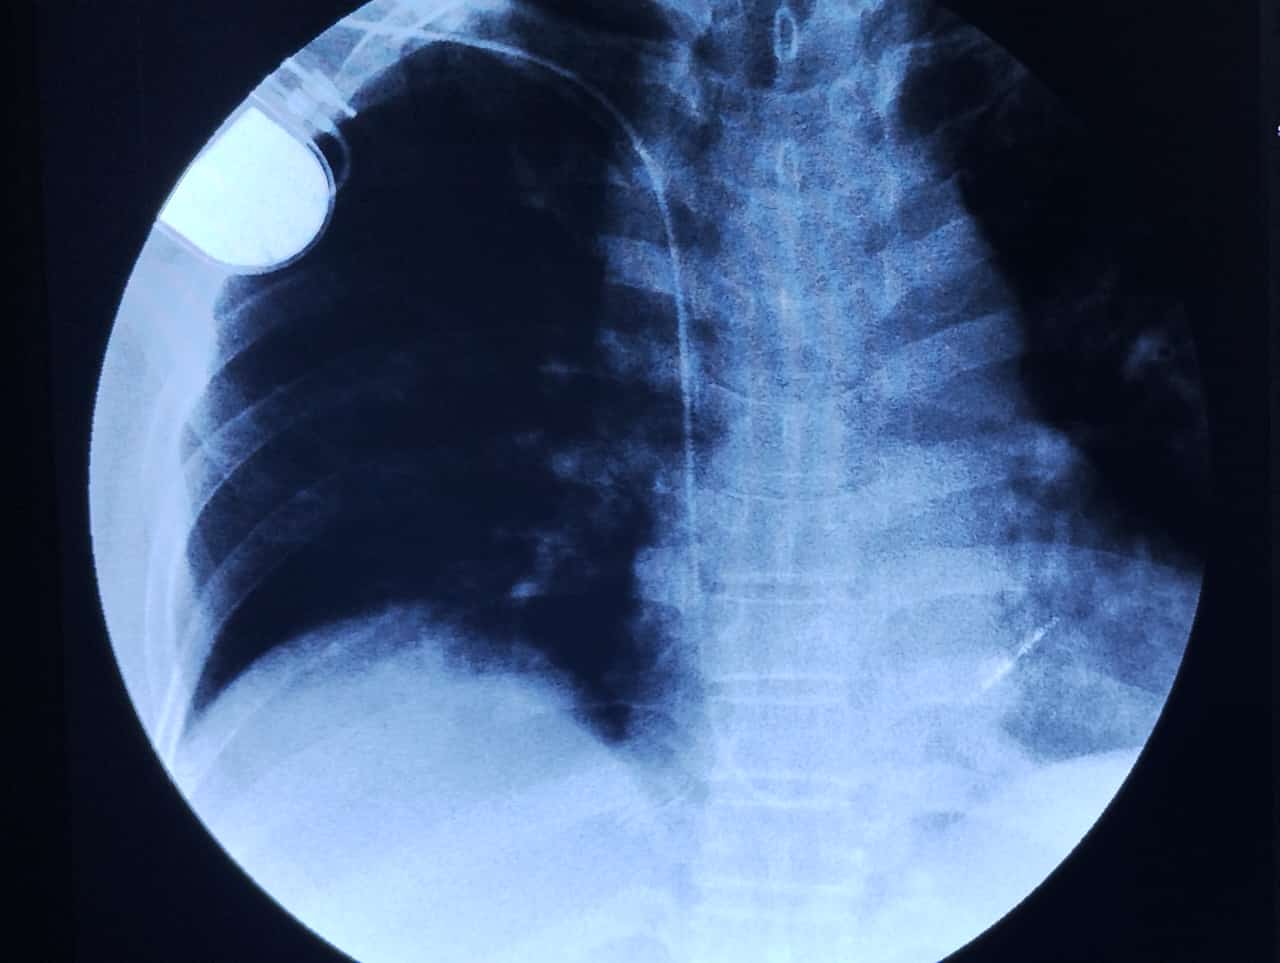

Gracias al apoyo e interés de las autoridades del Instituto Mexicano del Seguro Social (IMSS) en Veracruz Sur, el Hospital General de Zona (HGZ) No. 8, en Córdoba, reanudó el programa de marcapasos definitivos con la rehabilitación de la sala de Fluoroscopia, además de la implementación y adquisición de marcapasos temporales para el servicio de urgencias. El cardiólogo del HGZ No. 8, doctor José Antonio Pérez Muñoz resaltó que a nivel nacional este Hospital General de Zona es el único en realizar este procedimiento, mismo que generalmente se realizan en hospitales de tercer nivel, pero que desde la incorporación de este proyecto ha beneficiado con un total de 277 marcapasos definitivos. Pérez Muñoz refirió que este programa no solo es la colocación de los dispositivos, sino también la vigilancia y seguimiento del mismo, ver que funcione bien, y analizar cómo el uso desgasta la batería para que en el momento necesario se programe de forma oportuna el recambio del generador. Explicó que este procedimiento se realiza en pacientes que debido a padecimientos crónico-degenerativos presentan frecuencias cardiacas bajas, lo que ocasiona poca oxigenación al cerebro y a su vez que el paciente pueda presentar eventos de bajo gasto cerebral, sensación de mareo, lipotimias e incluso desmayos. Añadió que la vida de un marcapasos es de entre 8 y 12 años, pero esto depende de la marca, el modelo y el desgaste que el paciente le dé, ya que existen pacientes que sus trastornos del ritmo son intermitentes y no siempre entra en acción el equipo y hay otros que lo ocupan al 100 por ciento, o más constantemente, por eso se da el seguimiento anual. El médico indicó que el programa de marcapasos inicio en 2016 y aunque durante el 2021 se estuvo en pausa debido a una incapacidad laboral por una hemorragia cerebral que el mismo presentó, al día de hoy el hospital ha colocado 277 marcapasos contribuyendo a la reducción de tiempos de espera. La reactivación de este programa se dio con un recambio de marcapasos del paciente Rafael, de 62 años, beneficiándolo de manera inmediata, evitando con ello el envío a otra ciudad que tendría un costo de traslados, viáticos y del tiempo de espera. "En 2009 empecé con problemas cardiacos, una vez más el doctor Pérez me hizo el cambio y anteriormente también él me lo colocó aquí en Córdoba, ahorrándome todos los inconvenientes de los traslados, viajes y todo lo que conlleva toda esta situación. Hemos sido afortunados mi familia y yo por las atenciones recibidas por parte del IMSS", expresó el señor Rafael.